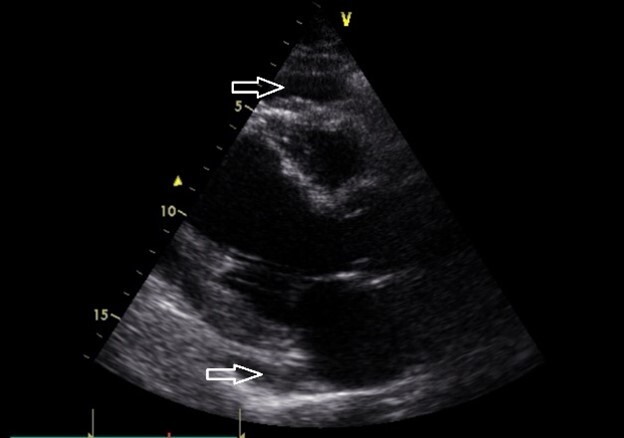

We present two cases of pericardiocentesis due to anorexia nervosa in young women.

A twenty-year-old and a twenty-four-year-old female with a history of anorexia nervosa were admitted to the cardiac surgery department due to pericardial effusions.

Both cases needed urgent pericardiectomy. Our patients did not show any signs of acute heart failure during the hospitalization. Due to their primary diagnosis, they needed psychological support and their food intake required monitoring.

Pericardial effusions are common in adolescent AN patients, and echocardiography monitoring is necessary to prevent the progression of acute cardiac tamponade.